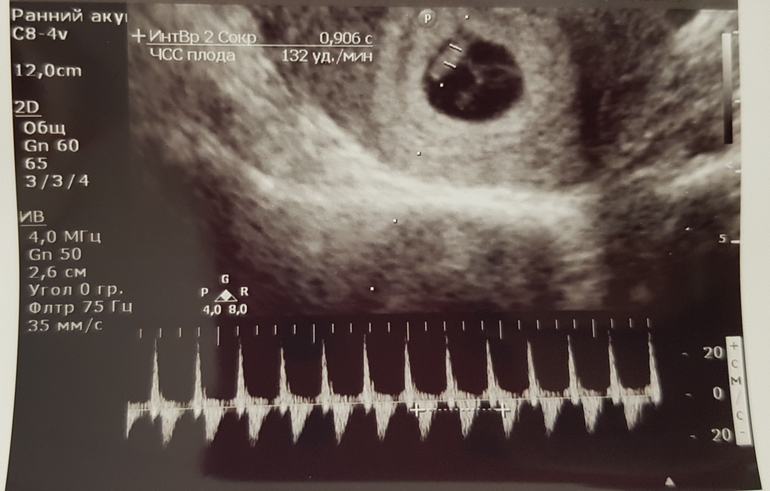

Узи 6нед 5 дн

Сегодня была на узи, где увидели нашу креветочку и дали послушать сердечко (КТР 8 мм, сб 132 удара/мин.), это незабываемо!!! До этой стадии я никогда не доходила, все время либо В либо ЗБ были, а тут включили на аппарате сердечко послушать и я просто в шоке до сих пор, поверить не могу, что все со мной происходит и что у меня внутри маленький, но такой важный чУловечек живет))))